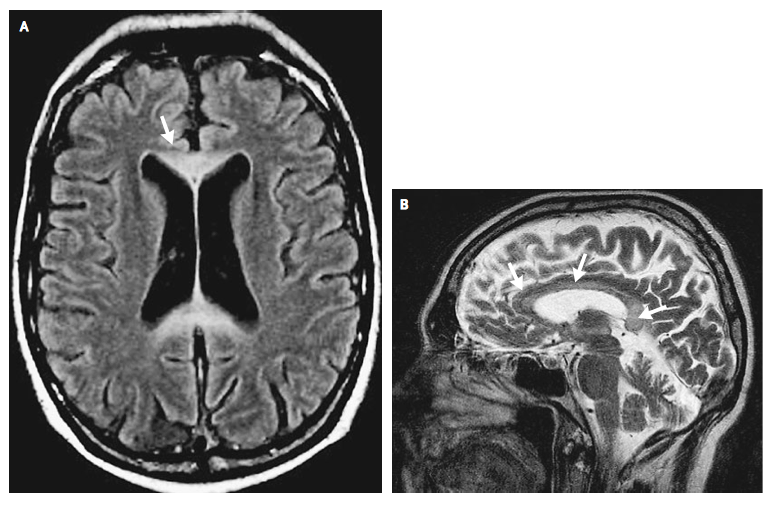

アルコールとうつ、自殺 アルコールと認知症 アルコールと癌(がん) アルコールと歯科疾患 アルコールの消化管への影響 アルコール性肝炎と非アルコール脂肪性肝炎 アルコールと痛風 アルコールと糖尿病 アルコールと高脂血症 胎児性アルコール症候群. 我慢できないほど、イライラ感が募るとき、「むくみ」がひとつの原因であることに気付いた。それから、イライラ感を処理するのが上手になった。 最初は「塩分の取りすぎ」を疑っていた 私は、食べたもので、気分が左右されやすい。時々、人が変わったようにイライラしてしまうことが. 脳mri画像 アルコール性ウェルニッケ脳症(t2強調画像) 中年の男性。以前からお酒が好きで止められず、大量に飲酒した後、意識がもうろうとし昏睡状態に陥りました。.

解答 解説 アルコール依存症の30歳代女性 実践 画像診断q A 羊土社 レジデントノート 羊土社